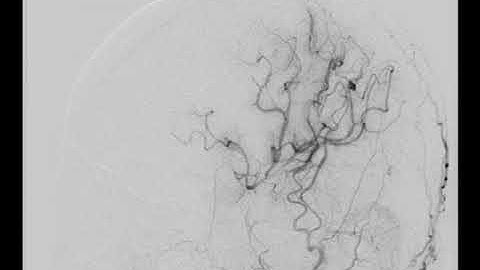

STA-MCA Brain Bypass Recovery, What to Expect out to week 11